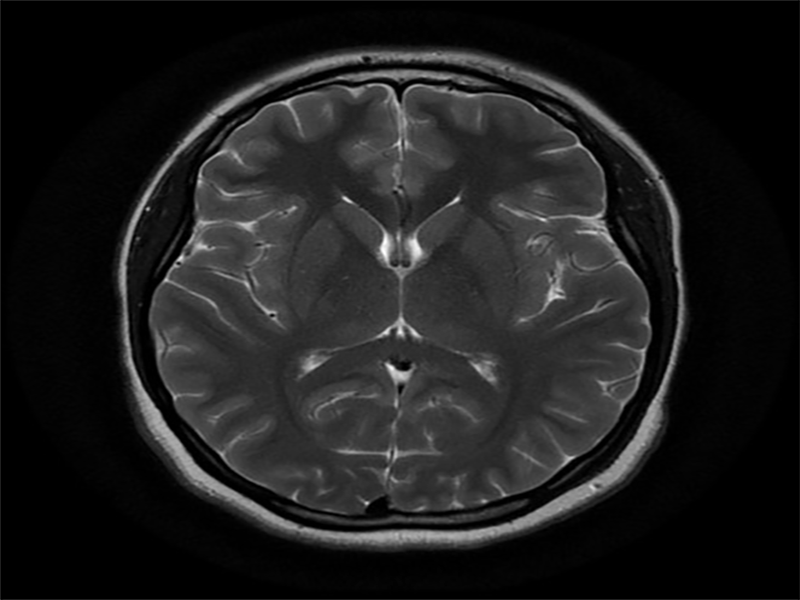

یکی از مهمترین بخشهای تشخیص این بیماری، این است که مشخص شود آیا نقطهای کانونی وجود دارد یا نه؛ یعنی بخش خاصی از مغز که تشنج از آنجا شروع میشود. این تشخیص کمک بزرگی به درمان بیمار میکند. ازجمله آزمایشهایی که برای تشخیص این اختلال از فرد گرفته میشود، میتوان به آزمایش خون، MRI، آزمایش مایع نخاعی، نوار مغز و سیتی اسکن اشاره کرد.